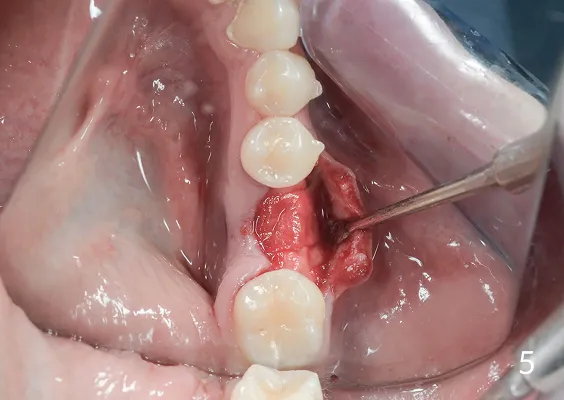

Sterowana regeneracja kości GBR przy użyciu biomateriałów oraz membran zaporowych. Procedury te są stosowane w sytuacji niedostatecznej ilości kości, skutkującej odsłonięciem gwintu, podczas gdy wszczepiamy implanty stomatolo-giczne lub też jako zabiegi poprzedzające ich wprowadzenie.

To technika pionowego rozszczepienia wyrostka zębodołowego przy użyciu osteotomów. Jest to delikatna technika zabiegowa stosowana w sytuacji braku dostatecznej ilości kości na szerokość. Polega na rozszczepieniu pionowym zanikłego w wymiarze horyzontalnym/poprzecznym wyrostka zębodołowego.

Zabiegu rozszczepienia dokonuje się przy użyciu Piezosurgery, specjalnych zestawów osteotomów lub dłut, którymi rozcina się i rozchyla kość zanikłej części zębodołowej żuchwy lub szczęk.

Pomiędzy rozchylone okładki kostne wprowadza się implanty, uzupełniając materiałem kościotwórczym pozostałą szczelinę w wyrostku. Należy w sposób właściwy dobierać i kalibrować instrumentarium, by nie spowodować uszkodzeń związanych z odłamaniem rozszczepianego fragmentu kostnego.